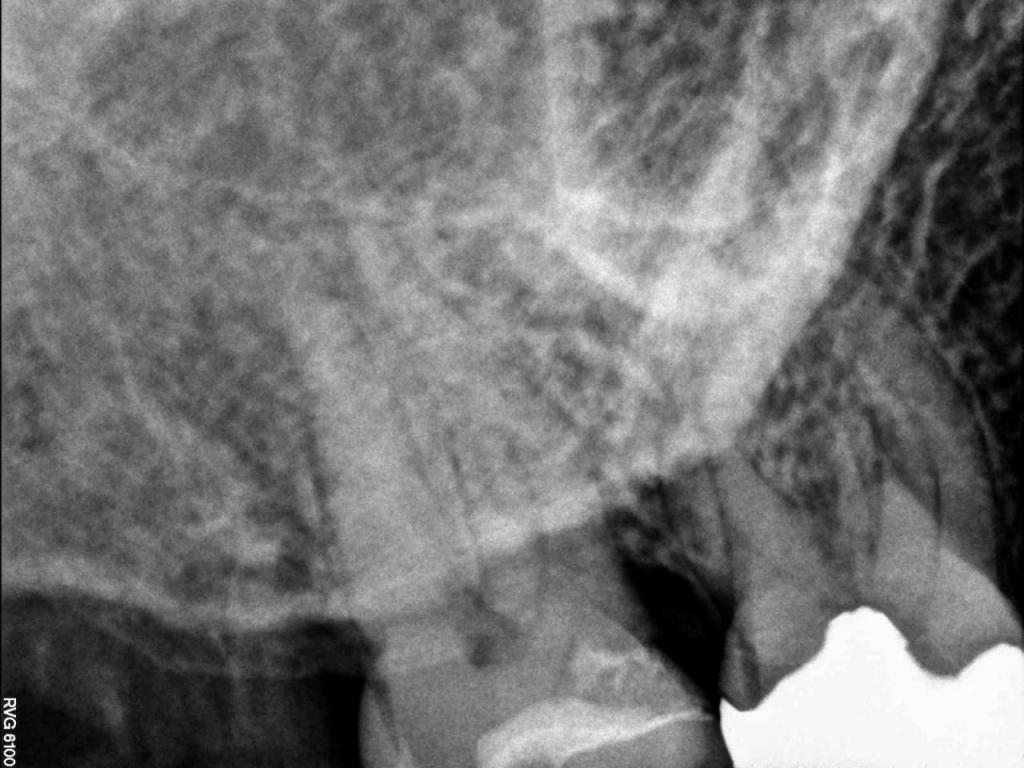

Although the primary use of visual documentation is for patient charts, dental images provide a meaningful way to communicate with patients about their care needs. Digital imagery is a vital tool for educating patients and an essential way to share information with office staff, colleagues and referring doctors. Digital technology has allowed Southcenter Endodontics to enhance our practice and improve the delivery of care to our patients. Below you will see images of “Before” and “After” scenarios. By clicking on a thumbnail image below, you will be able to see and a larger view of the x-ray taken at Southcenter Endodontics and notations made regarding each film.